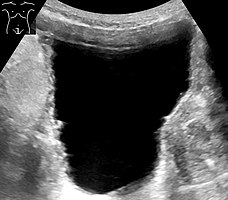

Analysis of urine flow may aid in establishing the type of micturition (urination) abnormality. Common findings, determined by ultrasound of the bladder, include a slow rate of flow, intermittent flow, and a large amount of urine retained in the bladder after urination. A normal test result should be 20-25 mL/s peak flow rate. A post-void residual urine greater than 50 ml is a significant amount of urine and increases the potential for recurring urinary tract infections. In adults older than 60 years, 50-100 ml of residual urine may remain after each voiding because of the decreased contractility of the detrusor muscle.[4] In chronic retention, ultrasound of the bladder may show massive increase in bladder capacity (normal capacity is 400-600 ml).

Non-neurogenic chronic urinary retention does not have a standardized definition; however, urine volumes >300mL can be used as an informal indicator.[4] Diagnosis of urinary retention is conducted over a period of 6 months, with 2 separate measurements of urine volume 6 months apart. Measurements should have a PVR (post-void residual) volume of >300mL.[4]